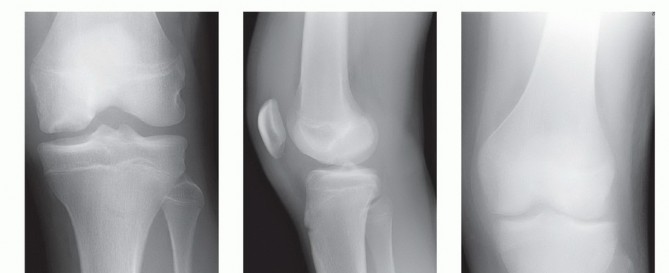

Osteochondritis Dissecans

In OCD, plain films help to localize and characterize the lesion while also providing valuable information regarding skeletal maturity and age of the lesion and ruling out other bony injuries.

Radiographic evaluation should include anteroposterior (AP), lateral, tunnel, and sunrise views (

FIG 6A,B

).

Tunnel views provide visualization of the femoral condyles in greater profile than can be obtained with AP views (

FIG 6C,D

). The tunnel view often is the most revealing view because OCD lesions commonly are located on the lateral aspect of the medial femoral condyle.

Comparison views of the opposite knee should be considered because 15% to 30% of cases are bilateral.

Magnetic resonance imaging (MRI) is an essential part of the diagnostic evaluation of OCD.

It provides critical information regarding the status of cartilage and subchondral bone, size of the lesion, presence of fluid beneath the lesion, extent of bony edema as well as loose bodies or other knee injuries (

FIG 6E,F

FIG 6 • A,B. AP and lateral views demonstrating a lesion in the medial femoral condyle. C,D. AP and tunnel views demonstrating an OCD lesion of the lateral femoral condyle. The femoral condyles are in greater profile in the tunnel view, making the lesion easier to appreciate. E,F. Coronal and sagittal MRI images of an OCD lesion. Note the joint fluid present beneath the lesion.